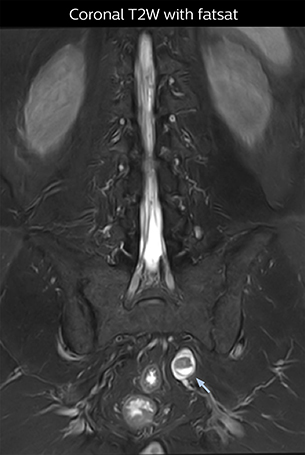

According to Tanji, methods such as ProSet FFE, STIR or 3D VISTA are anatomically nonselective because background signals, for instance from blood vessels, often interfere with nerves, which hampers evaluation of details, especially at the peripheral side of the nerves.

“The intra-luminal signal of veins, especially around the intervertebral space, can be suppressed well with NerveVIEW. As a result, we can easily observe the detailed nerve structure around the posterior ganglion,” he says. “This is why we use 3D NerveVIEW for intraforaminal stenosis and extraforaminal stenosis/herniation (lateral disc herniation). On the other hand, if herniation is suspected to exist inside the dorsal root ganglion (DRG), balanced TFE or ProSet-FFE is applied. NerveVIEW is not suitable for evaluating the median type of herniation.”

The SE-EPI DWI-based method for MR neurography works well for large FOV exams like whole-body MRI, but focal examination of nerves is often limited by the attainable spatial resolution (both inplane and slice direction) and geometric distortion. “3D NerveVIEW achieves higher in-plane resolution – close to our other routine spine sequences – and the source images can be used instead of adding a fat-suppressed T2-weighted sequence,” Tanji says.